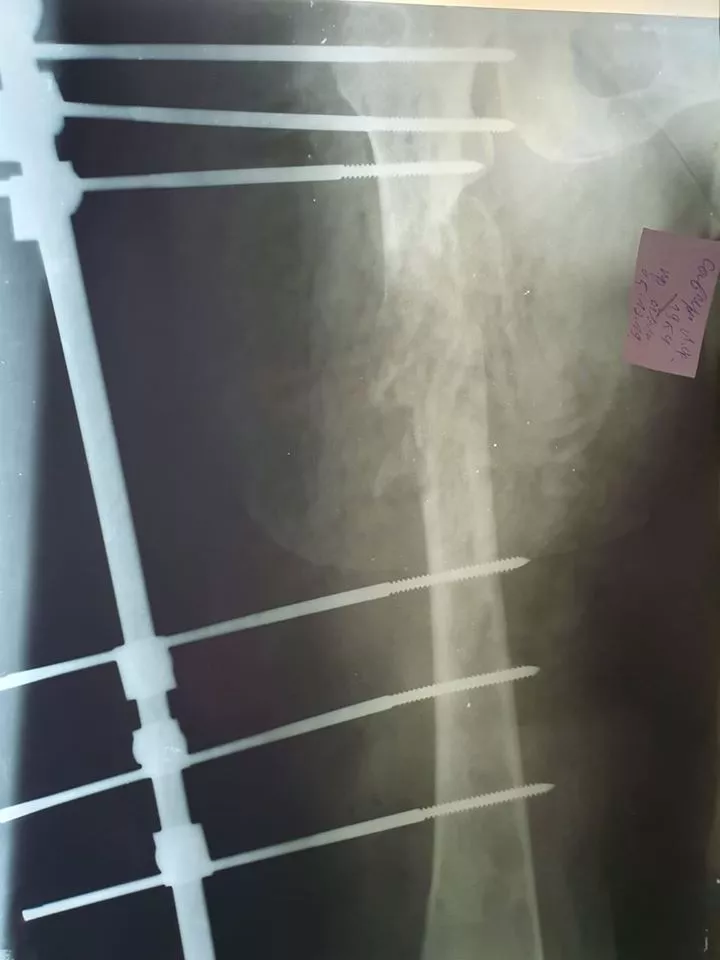

«В нас був один вихід: оскільки пластину вставити у стегно на зламі кістки було неможливо (цей метод фіксації був протипоказаний), довелося ставити апарат зовнішньої фіксації. Операцію проводили малоінвазивно, що вдалося уникнути крововтрати.

«Встановили шість зовнішніх стержнів у стегнову кістку, не зачепивши важливих судин і артерій, фактично довірившись чутливості своїх пальців», – доповнює свого колегу лікар Микола Абрамчук.

Тривала операція півтори години, під час якої лікарі вправили місце перелому та зафіксували його за допомогою апарату зовнішньої фіксації (зовнішніми металевими штирями).